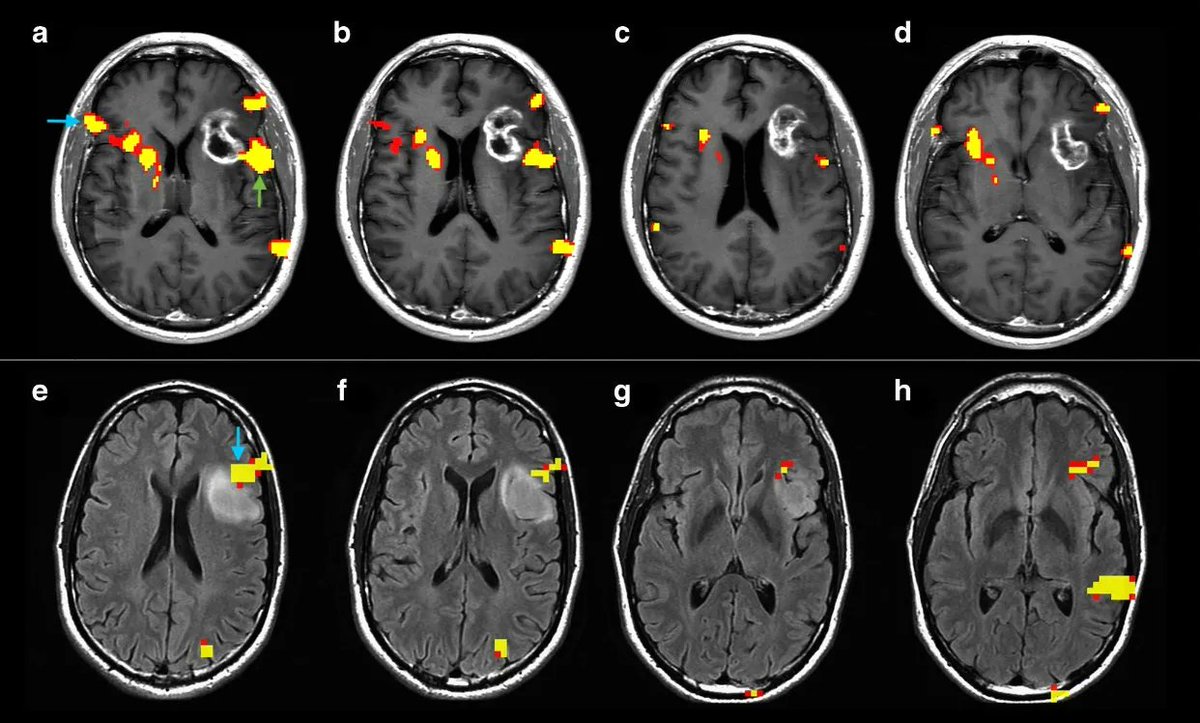

Language lateralization from Resting State fMRI? Syed Rakin Ahmed Syed Rakin Ahmed shows you how! pubmed.ncbi.nlm.nih.gov/37032593/

#Tumor location, grade, and genetics may influence language plasticity, affecting both communication between eloquent areas and tumor growth dynamics. (Luca Pasquini MD, PhD et al., Sapienza Università di Roma, Memorial Sloan Kettering Cancer Center ) 🔗 buff.ly/3Aut1LX #EuropeanRadiology #OpenAccess

🥇Check out the Editor's Choice #Article "Brain Functional Connectivity in Low- and High-Grade Gliomas: Differences in Network Dynamics Associated with Tumor Grade and Location" 🧐by Luca Pasquini MD, PhD, Mehrnaz Jenabi, et al. Memorial Sloan Kettering Cancer Center 🔗Link here: mdpi.com/2072-6694/14/1…